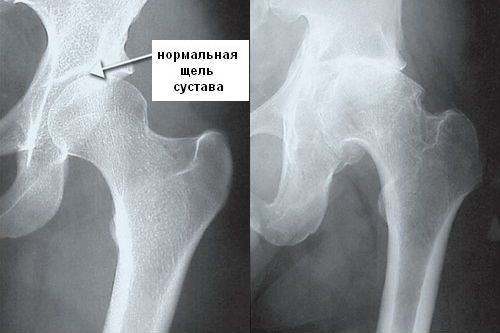

Остеосклероз тазобедренного сустава

Такая локализация склероза практически всегда осложняет течение артроза тазобедренного сустава. Больные жалуются на хроническую боль в бедре, которая сначала возникает при физической нагрузке, а затем беспокоит даже в покое. Постепенно амплитуда движений в суставе ограничивается, развивается хромота.

Если патологический процесс вовремя не купировать, то со временем сустав полностью разрушается, функция нижней конечности утрачивается. Такие пациенты смогут восстановить способность к самостоятельному передвижению только благодаря операции эндопротезирования тазобедренного сустава.

На второй рентгенограмме можно отметить отсутствие суставной щели в тазобедренном суставе и увеличение плотности субхондральной костной ткани, что является признаками коксартроза

Опасность склероза этой локализации заключается в повышении риска таких серьезных патологий, как перелом шейки бедренной кости и асептический некроз ее головки. Поэтому при выявлении остеосклероза тазобедренного сустава в первую очередь необходимо заниматься профилактикой возможных тяжелых последствий.